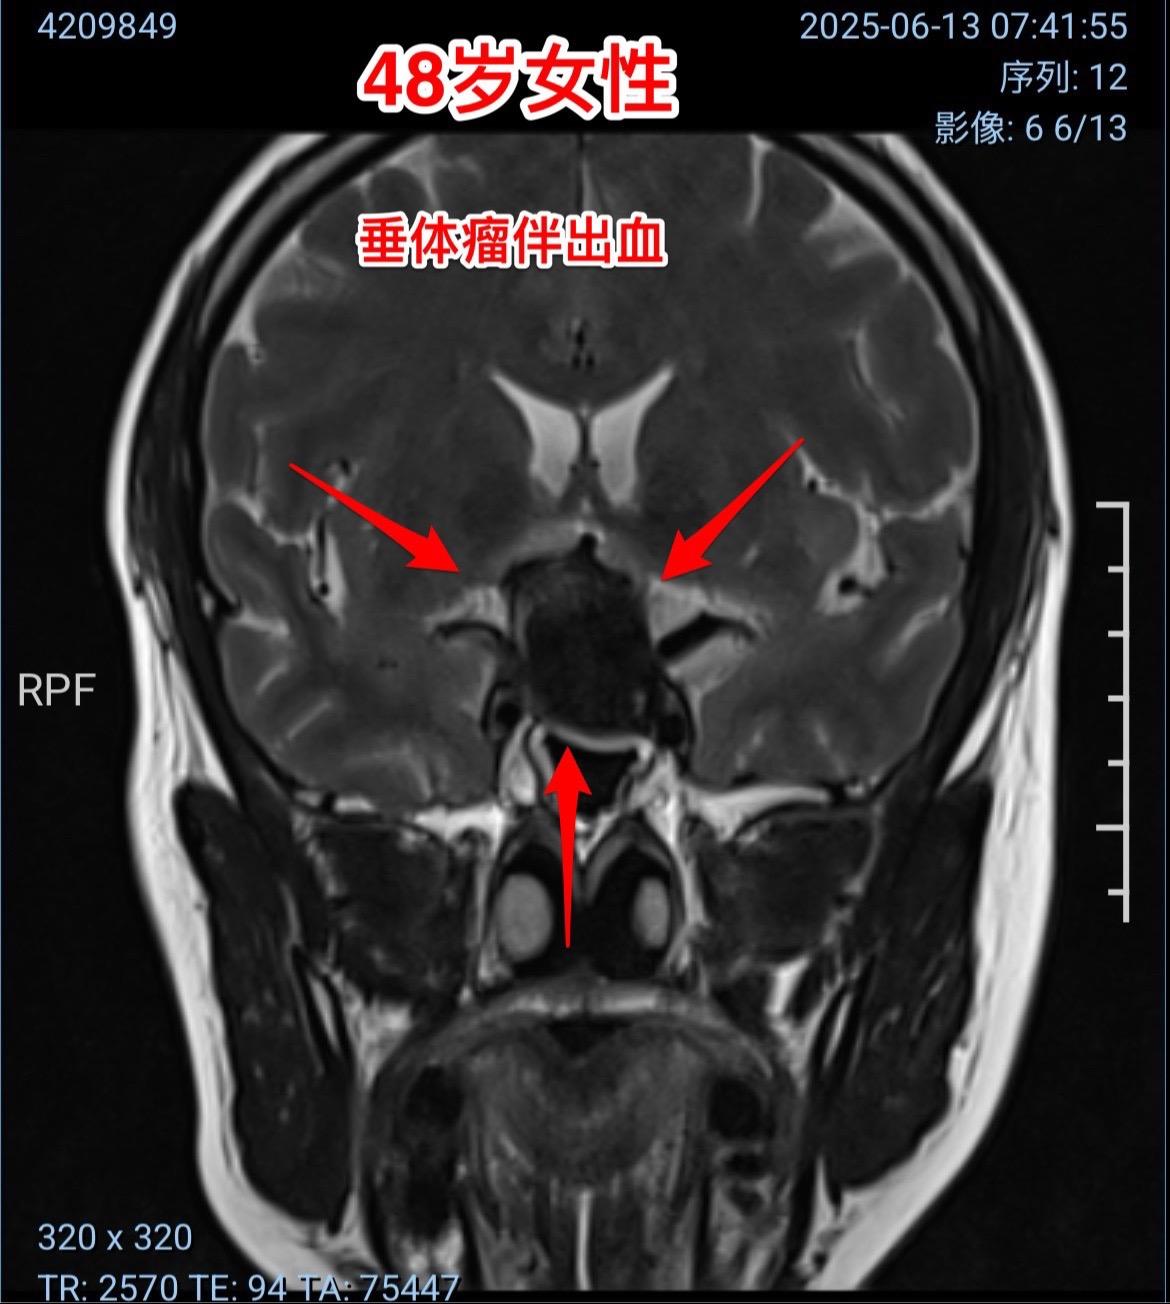

两个月内两个垂体瘤卒中 病例 垂体瘤卒中的最明显的症状是突发视力下降,可以伴有头痛。病人到医院眼科就诊一般找不出眼科的疾病,这时候只要作一个头部CT或者磁共振即可确诊垂体瘤卒中。一旦确诊,则应该尽快行手术切除垂体瘤,对视神经进行减压,争取挽救视力。 图1-6:男性,21岁,入院前六天突发视力下降,几乎双眼失明。在当地医院曾经怀疑是颅咽管瘤。在我科住院后给予激素治疗、对症治疗后视力呈现好转趋势。化验结果显示垂体功能低下(甲状腺激素低下、肾上腺皮质功能低下、性激素低下)。7月3日经鼻手术切除垂体